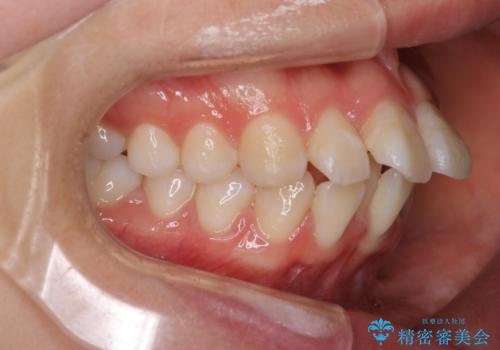

抜歯矯正をして口元を下げたことで、口元が下がりEラインが大変綺麗になりました。

矯正期間も1年9ヶ月と比較的短期間で終了することができました。